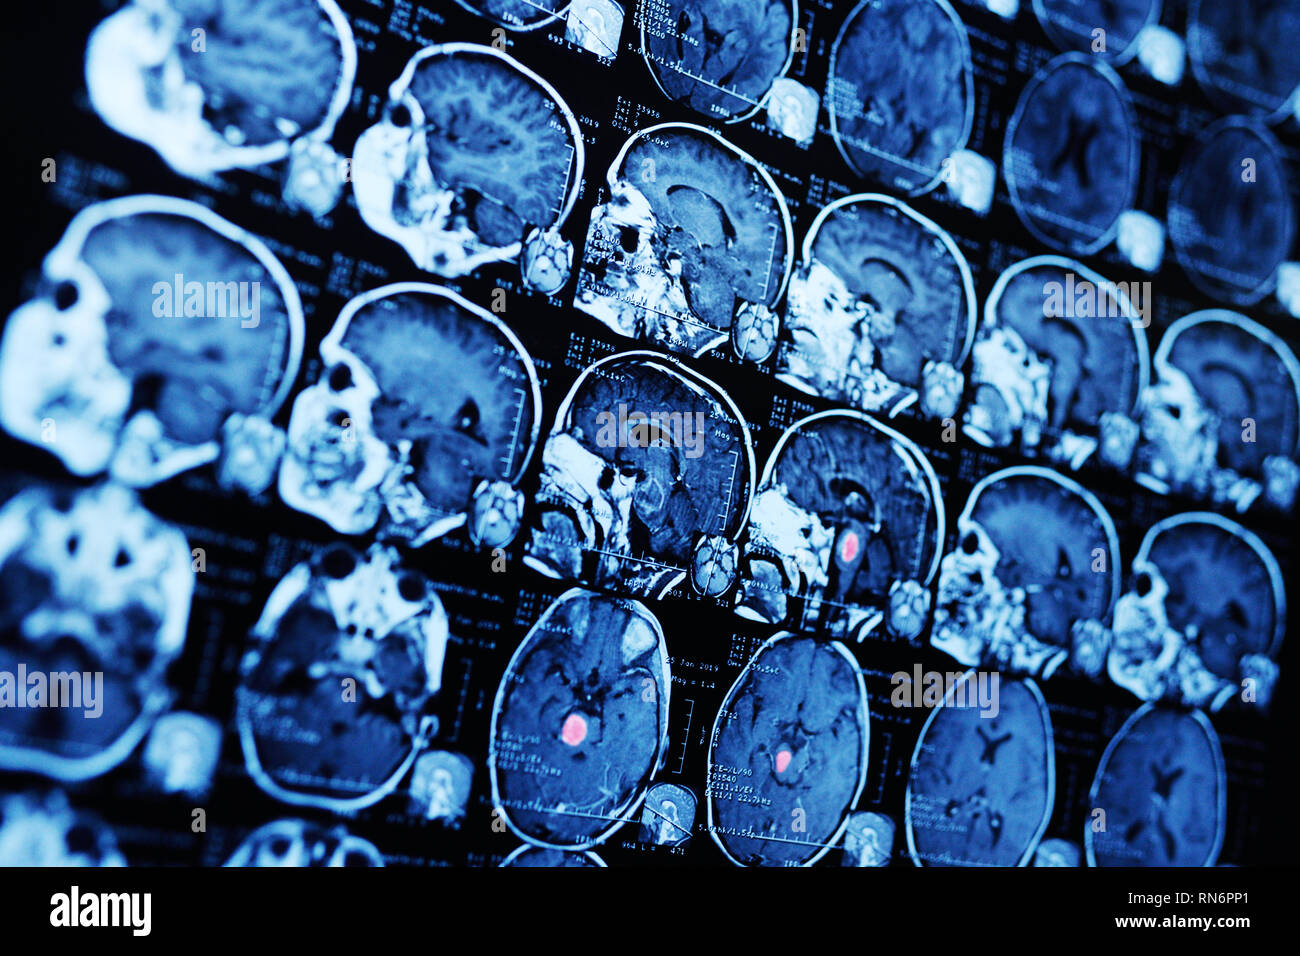

MRI magnetic resonance image scan of a patient with a tumor in the brain stem. Stock Photohttps://www.alamy.com/image-license-details/?v=1https://www.alamy.com/mri-magnetic-resonance-image-scan-of-a-patient-with-a-tumor-in-the-brain-stem-image236792137.html

MRI magnetic resonance image scan of a patient with a tumor in the brain stem. Stock Photohttps://www.alamy.com/image-license-details/?v=1https://www.alamy.com/mri-magnetic-resonance-image-scan-of-a-patient-with-a-tumor-in-the-brain-stem-image236792137.htmlRFRN6PP1–MRI magnetic resonance image scan of a patient with a tumor in the brain stem.